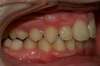

Intra Orale Droite